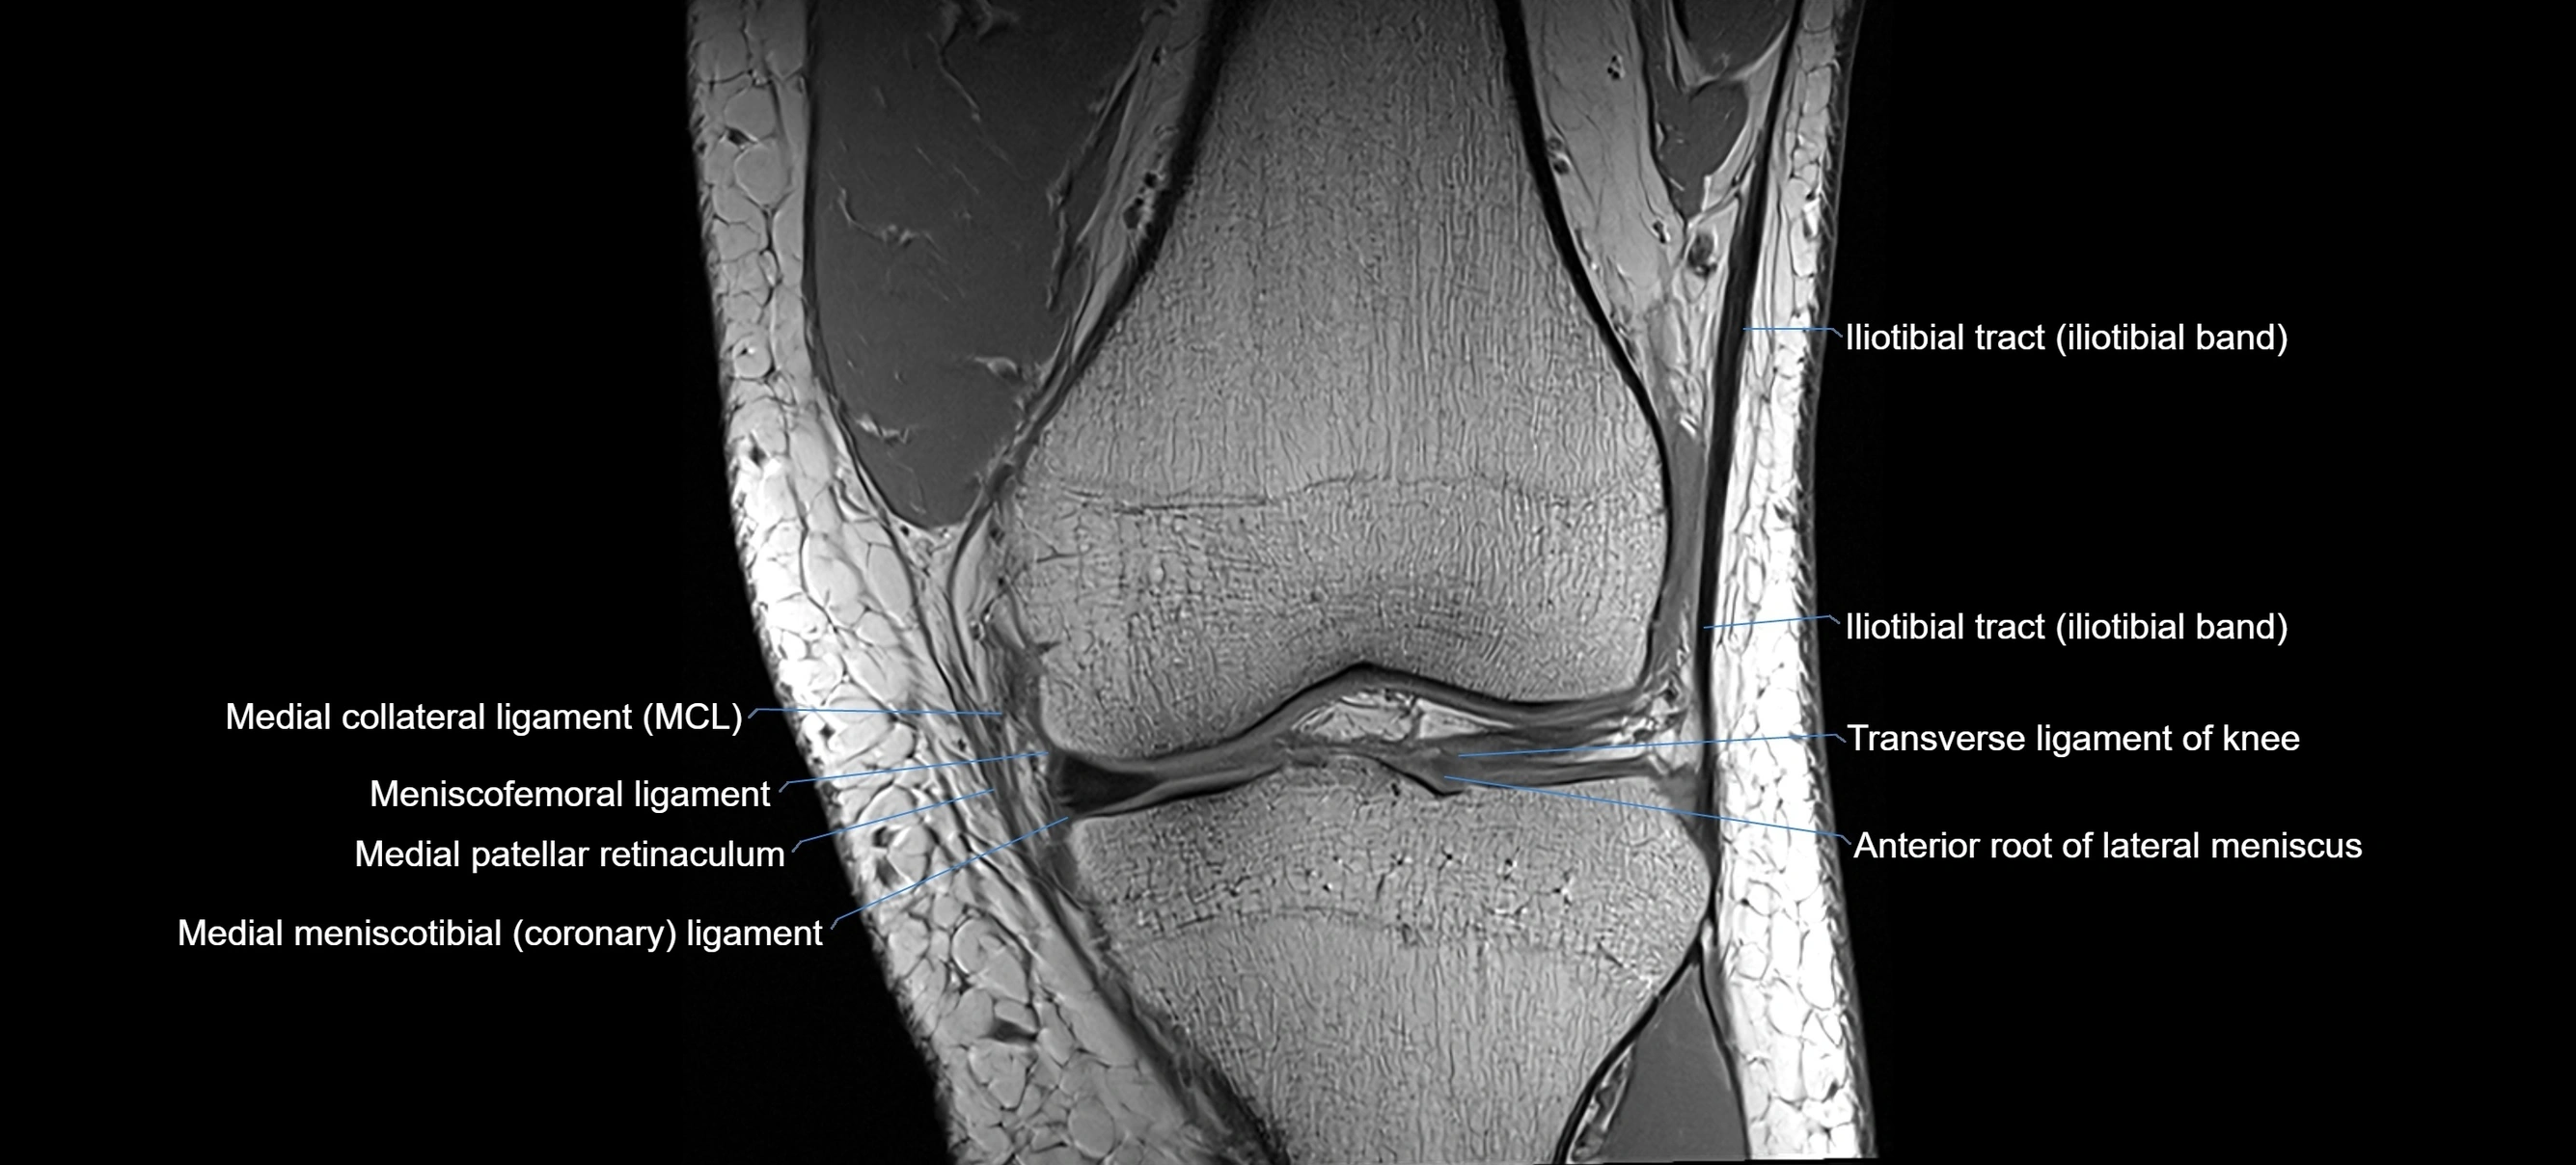

MRI images

image